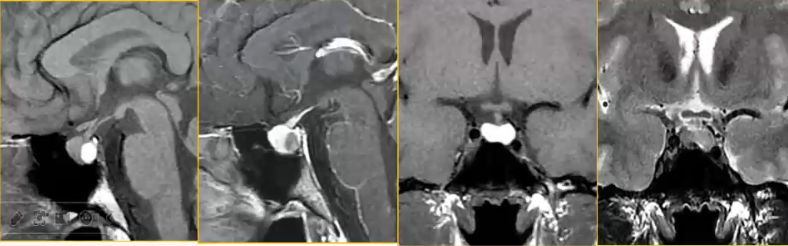

Rathke裂囊肿

Rathke囊肿是胚胎Rathke囊的上皮残余,壁薄,仅1-2层细胞;囊壁有分泌功能,液体增多形成囊肿。囊液可为浆液性或粘液性。可发生于任何年龄。部位:鞍上鞍内均存在(75%),鞍内(20-25%),仅在鞍上(<5%),典型部位在垂体前后叶间。

CT、MRI表现:

1. 垂体前后叶间的囊性病变

2. 囊肿信号与囊液的性质有关

3. 增强后无强化

Rathke裂囊肿位于垂体前后叶间,信号与囊液的性质有关,对前后叶及邻近结构产生压迫(如下图)